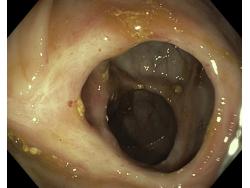

Obrazy endoskopowe

Choroba Leśniowskiego-Crohna